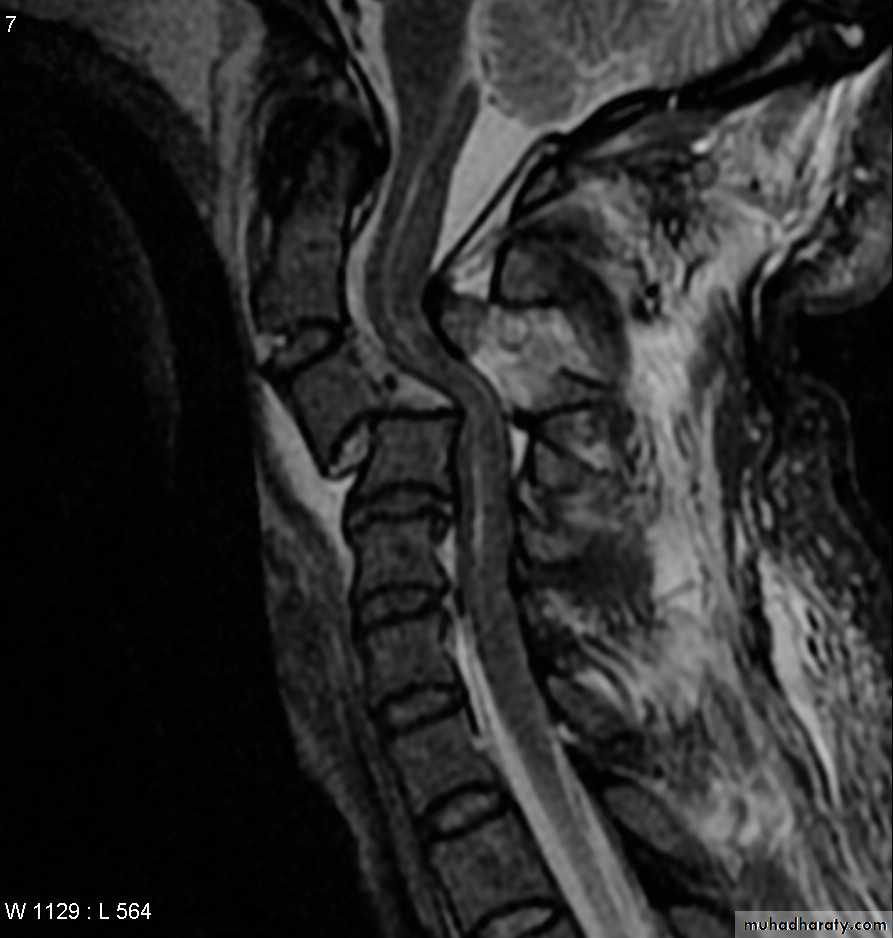

Computed tomography (CT)

frcature spine and peripheral nerve

and magnetic resonance imaging (MRI).

intraspinal displacement of soft tissue